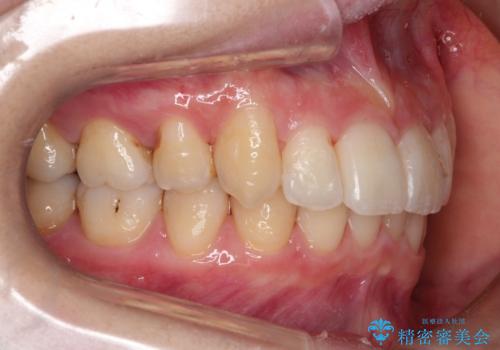

初診時の歯並びの状態としては、上下ともに前歯部の中等度のがたつきがあり、下の前歯は本来生えるはずの歯が2本生まれつき欠損している状態でした。

また、上顎の歯は虫歯で歯冠が崩壊してしまって保存不可能な歯がありました。

抜歯ありワイヤー矯正にて治療を行い、抜歯する歯に関しては虫歯で抜歯が必要な部分を有効活用することで、健康な歯を保存するように努めました。

噛み合わせが深い過蓋咬合という状態でもあったため、下の歯の装置をつけたり、嚙み合わせを上げる(下の歯が見える状態にする)ことにたいへんに苦労した症例でした。